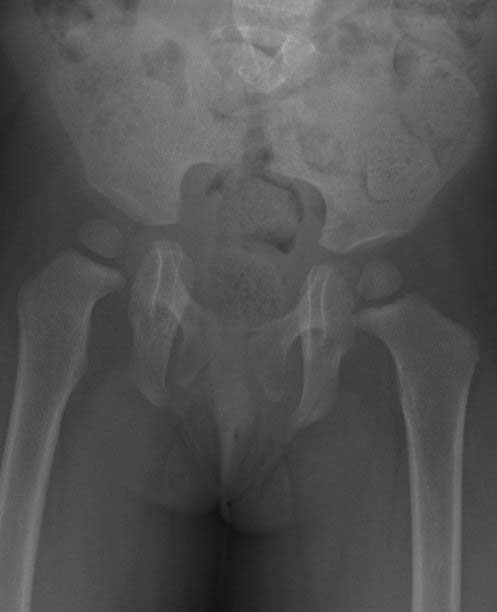

Plain x-ray image of a pediatric patient's pelvis. The image shows sacral agenesis (rare failure of sacral bone development).

Note: Images are shown for illustrative purposes. Do not attempt to draw conclusions or make diagnoses by comparing these images to other medical images, particularly your own. Only qualified physicians should interpret images; the radiologist is the physician expert trained in medical imaging.